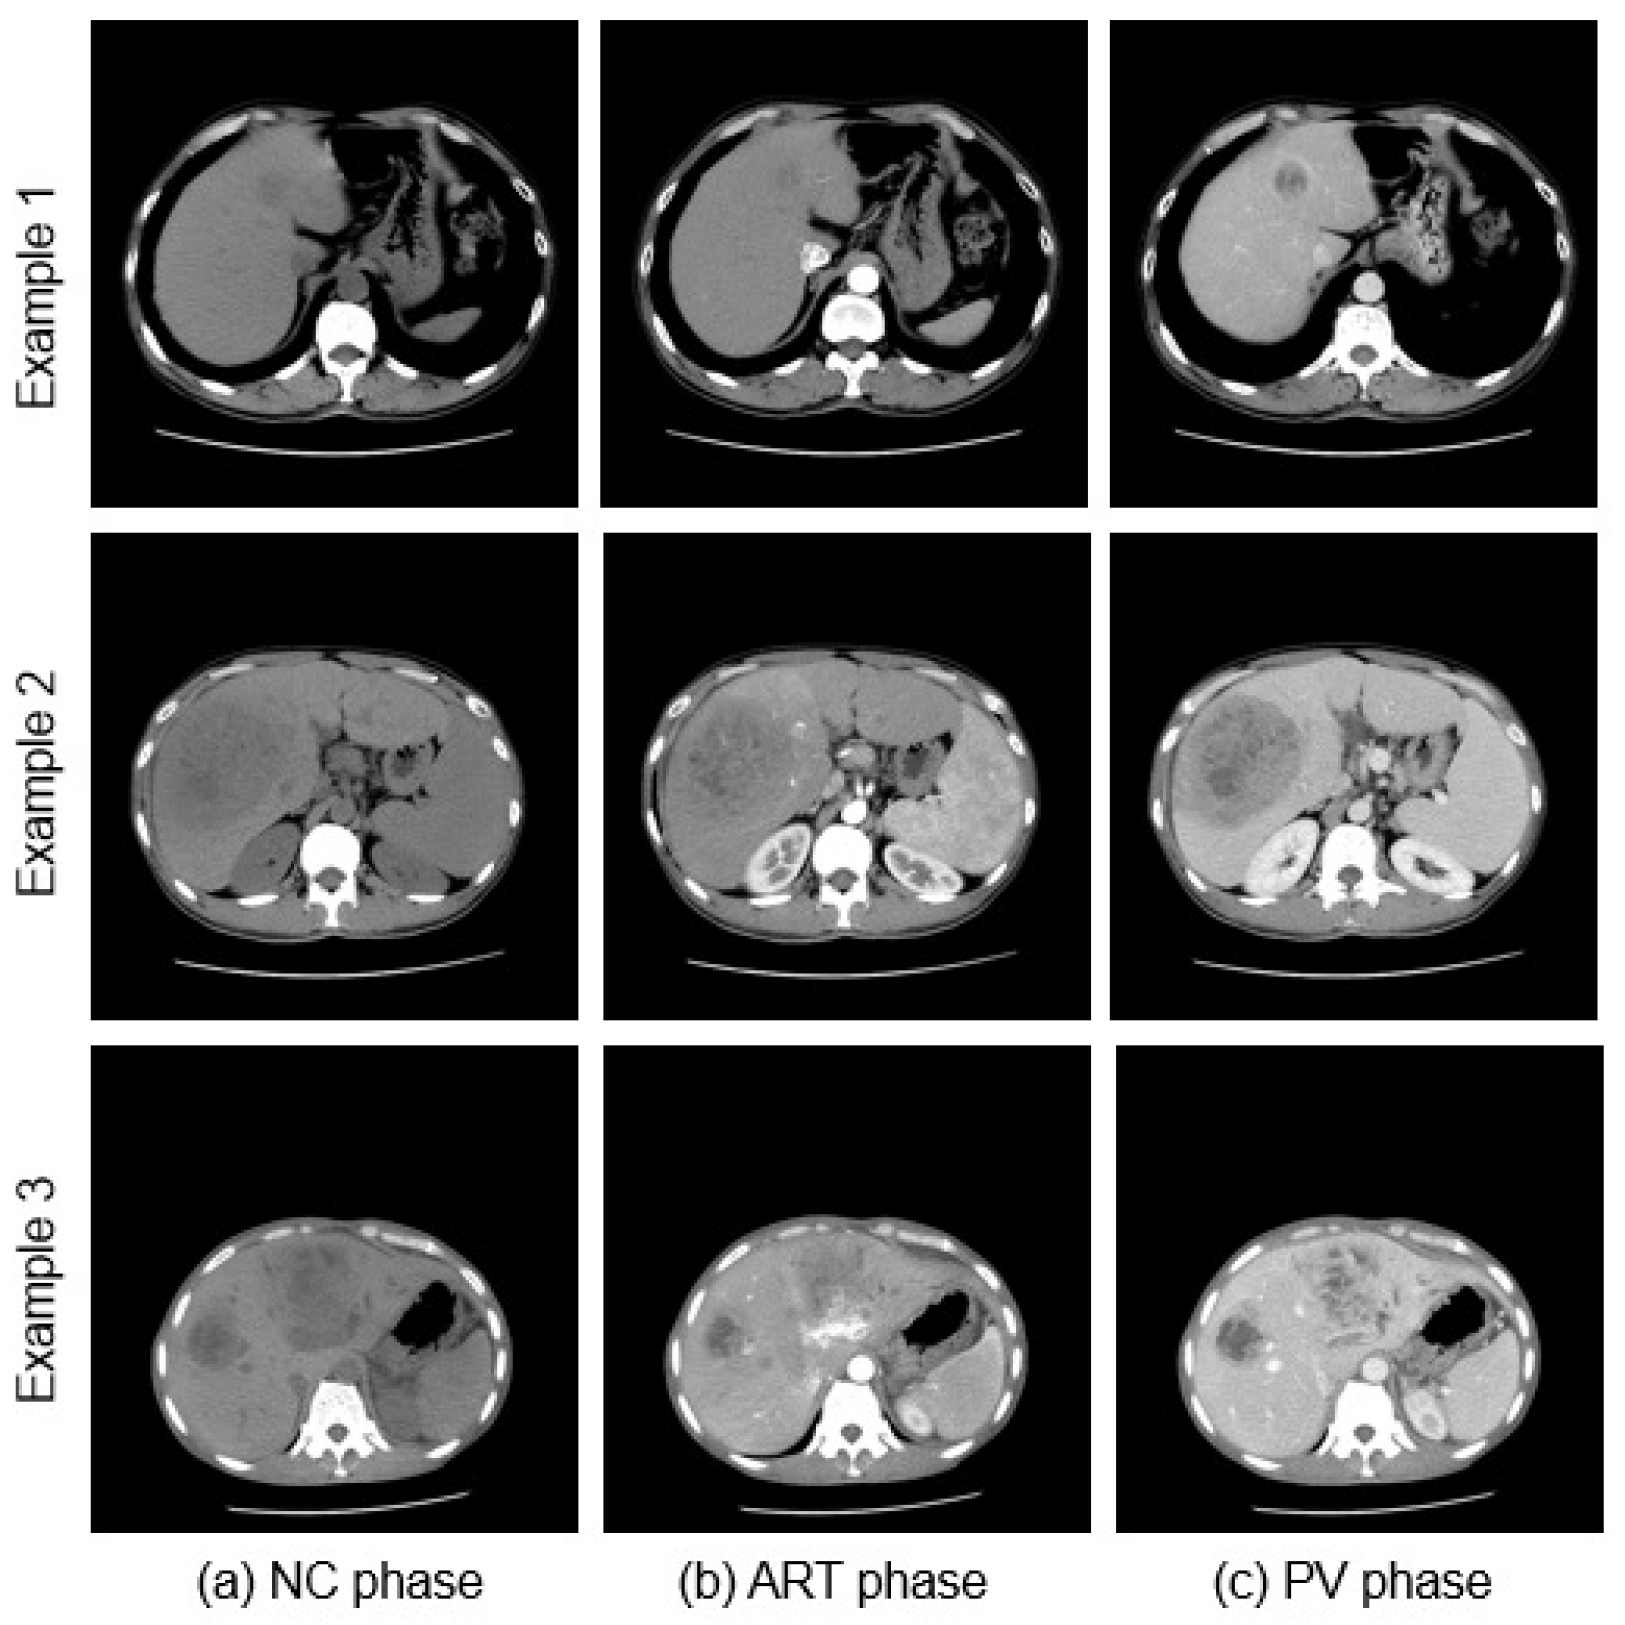

4.1. Dataset